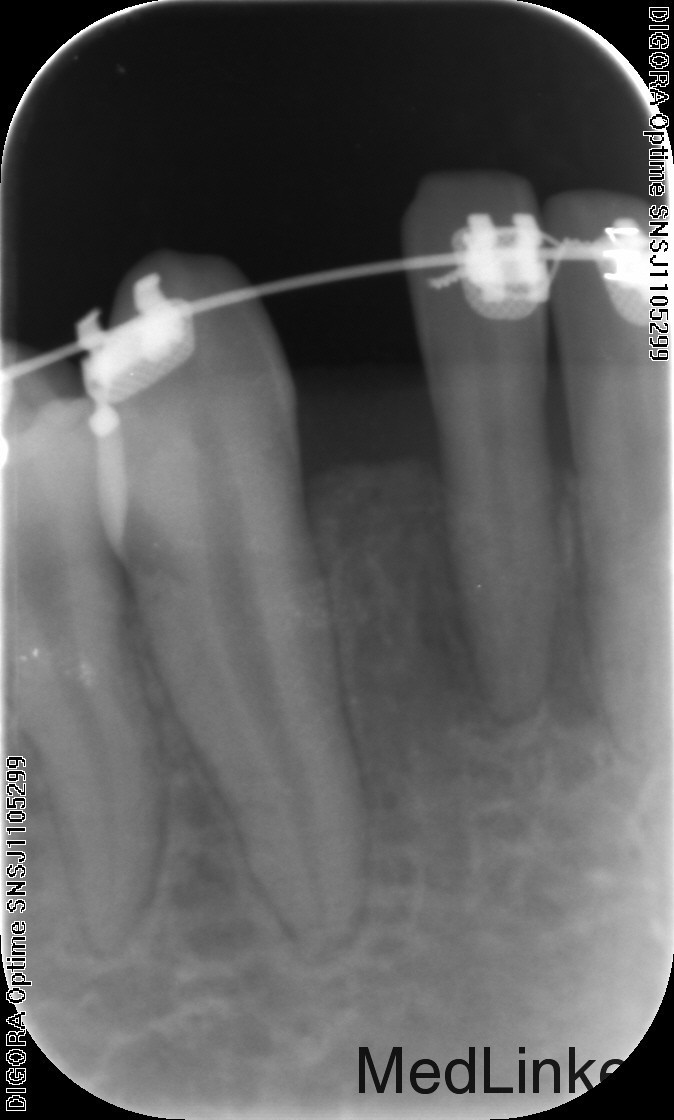

治疗:1、联合正畸科治疗,正畸科移动双侧中切牙至中线两侧后留出位置行种植治疗 2、常规消毒铺巾局部麻醉,切开翻瓣,植入Astra种植体3.0*8mm种植体两枚,严密缝合